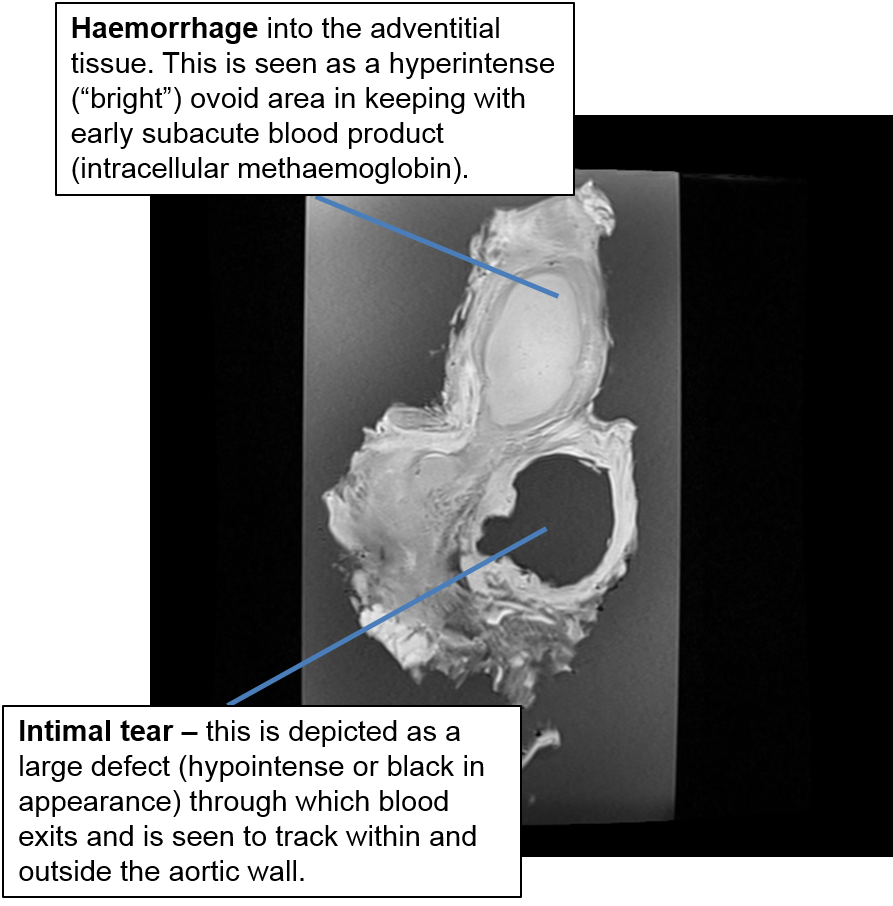

Aorta - Dissecting Aneurysm